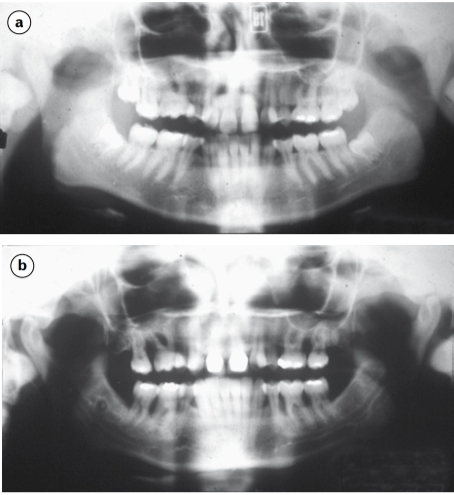

Study the two radiographs which are of the same

patient at (a) 19 years and (b) 34 years of age.

Generalised aggressive periodontitis. The severity

of bone resorption and the radiographic absence of

signs of resorption at 19 years preclude a diagnosis of

chronic periodontitis.